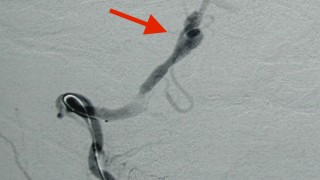

症例 高血圧の人、こんな頭痛は非常に危険だ! 突然の片側の後頭部痛 突発性の頭痛は、だいたいが危険であることが多いのです。そして、もしこれが片側だけに起こった場合には、「解離性椎骨動脈瘤」という病気を考える必要があります。解離性椎骨動脈瘤さて、この病気はあまり聞きなれないと思いますので要点をまとめて見たいと... 2015.11.27 症例症状